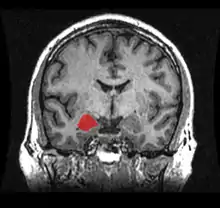

The diagnosis of temporal lobe epilepsy can include the following methods:[60] Magnetic resonance imaging (MRI), CT scans, positron emission tomography (PET), EEG, and magnetoencephalography.